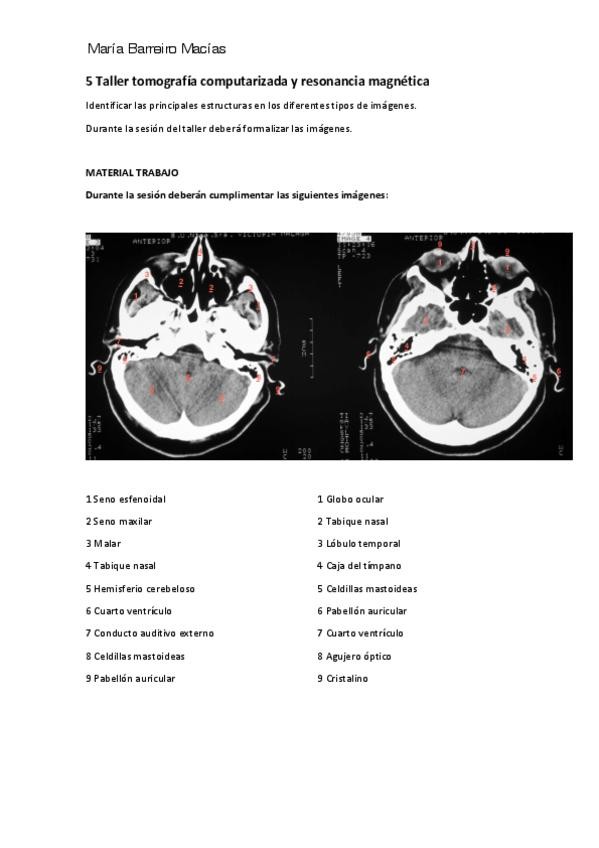

Talleres neuro 2020/2021

He publicado nuevos apuntes de 2º Anatomía II: cabeza y sistema nervioso central: Talleres neuro 2020/2021

TALLER-5-TC-y-RM-SNC.pdf

He publicado nuevos apuntes de 2º Anatomía II: cabeza y sistema nervioso central: TALLER-5-TC-y-RM-SNC.pdf

10 páginas